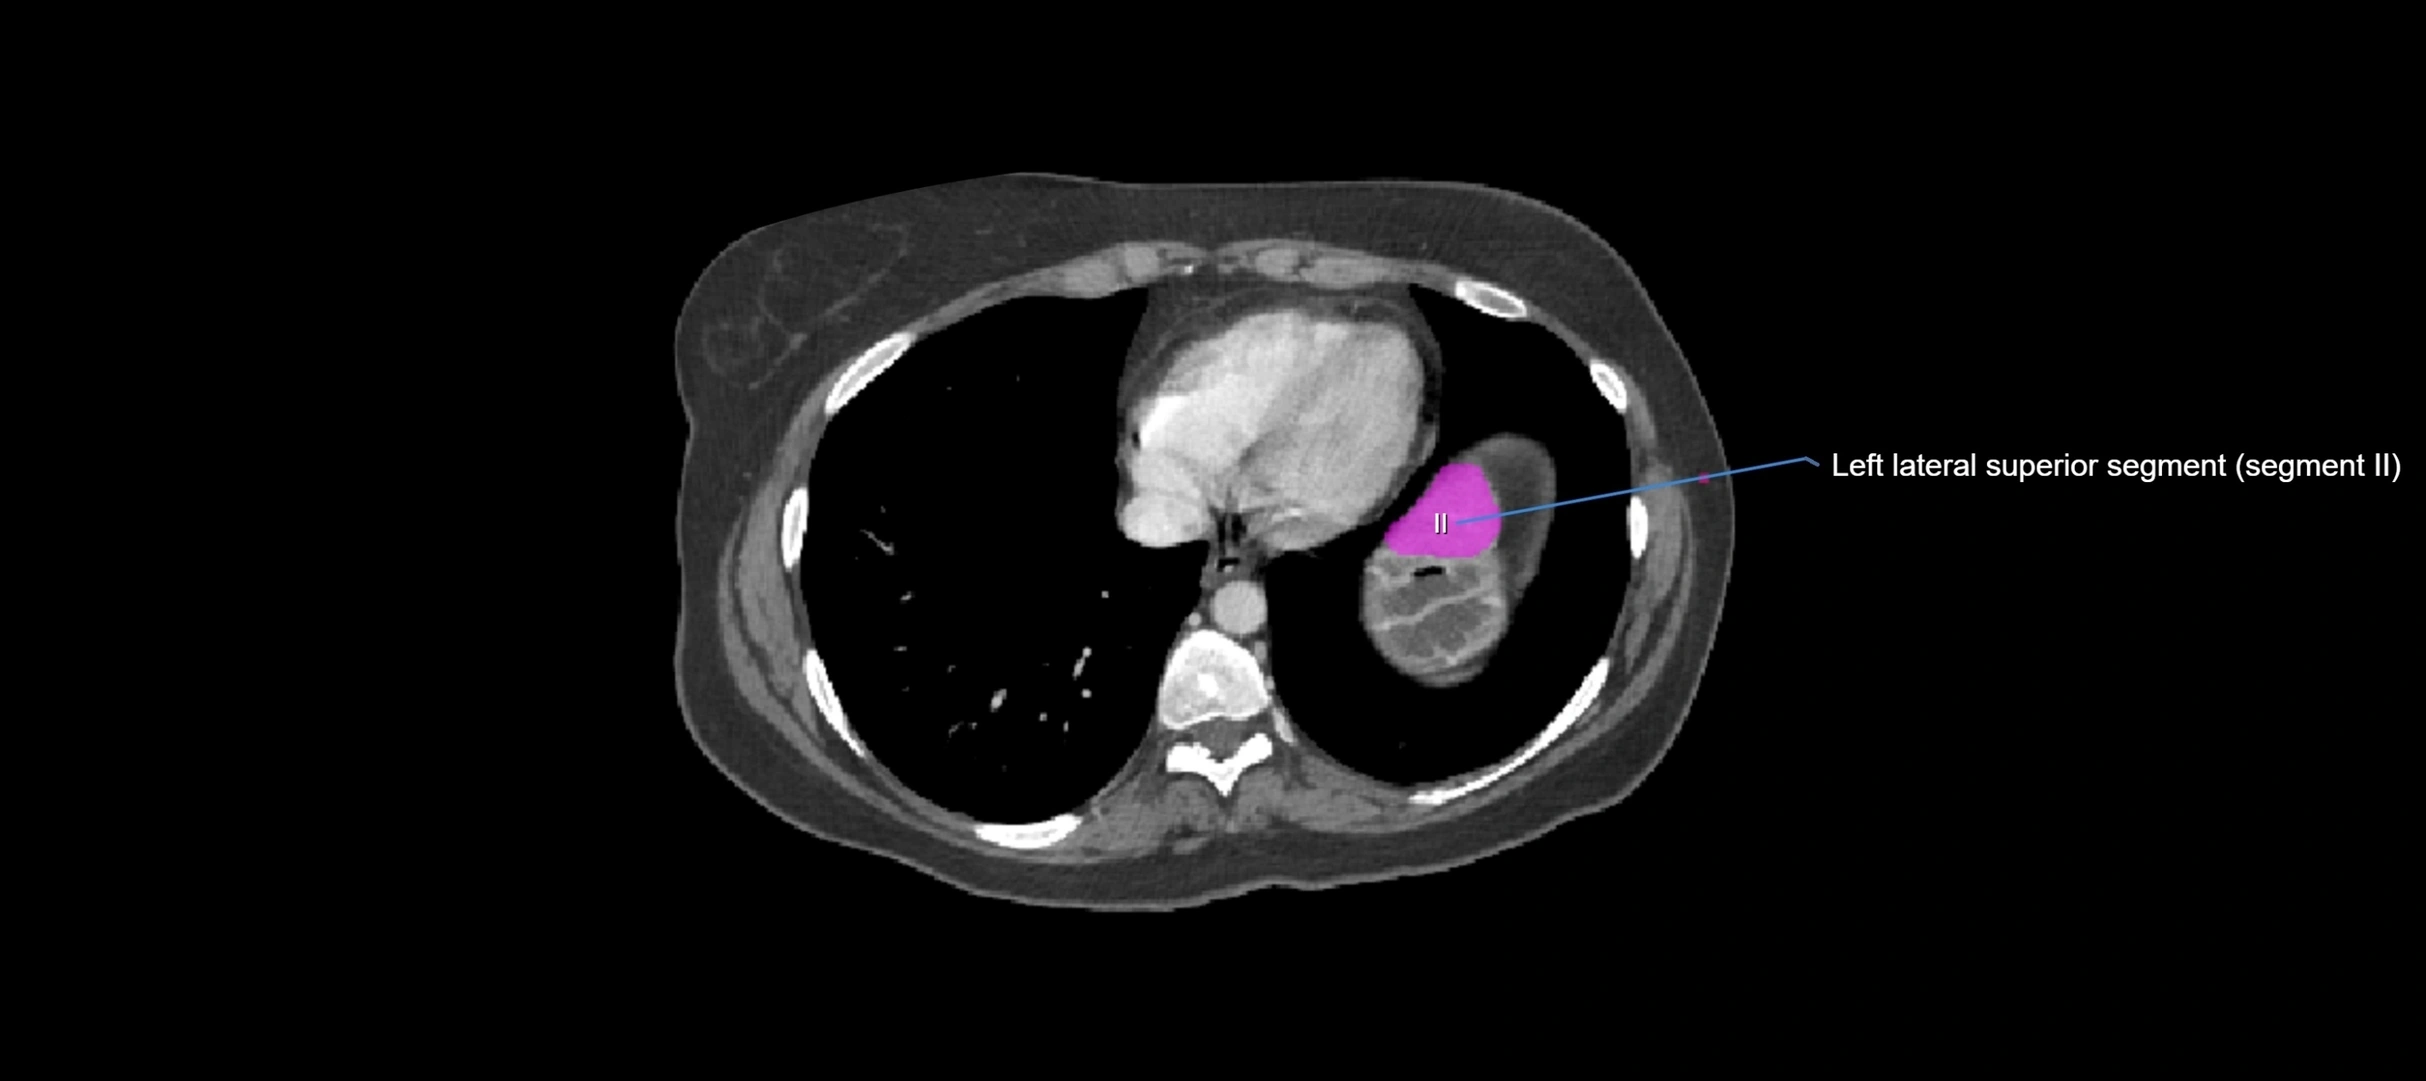

MRI image

image